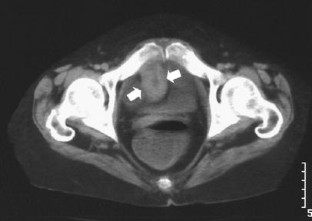

Crohn disease obstruction of the biliopancreatic limb in a patient operated for biliopancreatic diversion for morbid obesity

Although rare, patients with biliopancreatic diversion for morbid obesity will be subject to obstruction of the biliopancreatic limb. This condition is commonly due to postoperative adhesions and intussusception and usually presents with misleading clinical and radiographic features that can delay the diagnosis and the treatment. We recently encountered a patient with obstruction of the biliopancreatic limb due to involvement from Crohn disease. We report this case to highlight the clinical and imaging findings of this rare condition.

Fig. 1